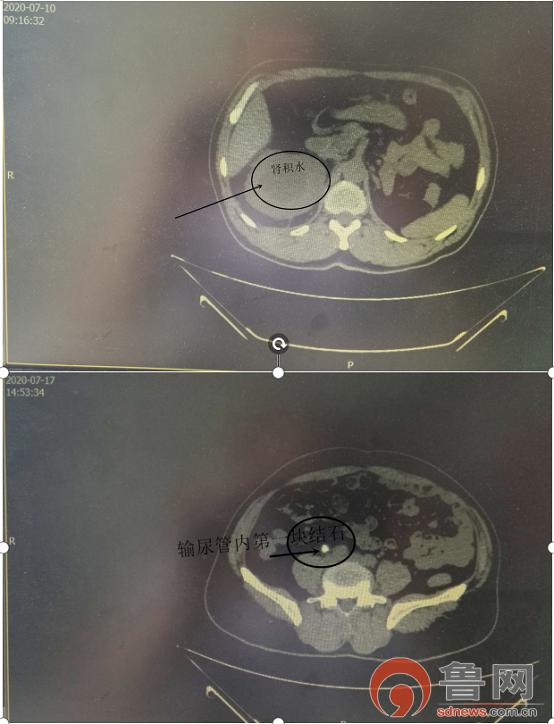

2020年3月新冠病毒疫情期间,患者宅在家中,喝水少、活动少,泌尿系结石再次复发,因为为孤立肾,手术风险高,难度大,加之疫情影响,患者辗转*安泰**市多家医院治疗,未能将结石碎除干净。于2020-07-10凌晨5点,患者因无尿、腰部胀痛急诊来*安泰**市中医医院,此前已24小时无尿,急性肾功能衰竭,入院诊断为:1.右侧输尿管结石并右肾积水2.右肾结石3.左肾切除术后4.急性肾功能衰竭。

患者入院后完善相关检查,发现输尿管内两块结石梗阻。排除手术禁忌后于2020-07-10急诊送手术室在蛛网膜下-硬膜外复合麻醉下行经尿道输尿管镜下右侧双“J”管置入术,手术顺利,术后患者尿量恢复,并进入多尿期,每日4000+ml,根据各项检查,患者支架管置管位置良好,肾功能已恢复正常,并于2020-07-21上午在蛛网膜下-硬膜外复合麻醉下行经尿道输尿管镜下钬激光碎石取石术,应用新的国产大族激光,将结石碎除干净,成功解决了患者令人头痛的泌尿系结石问题。